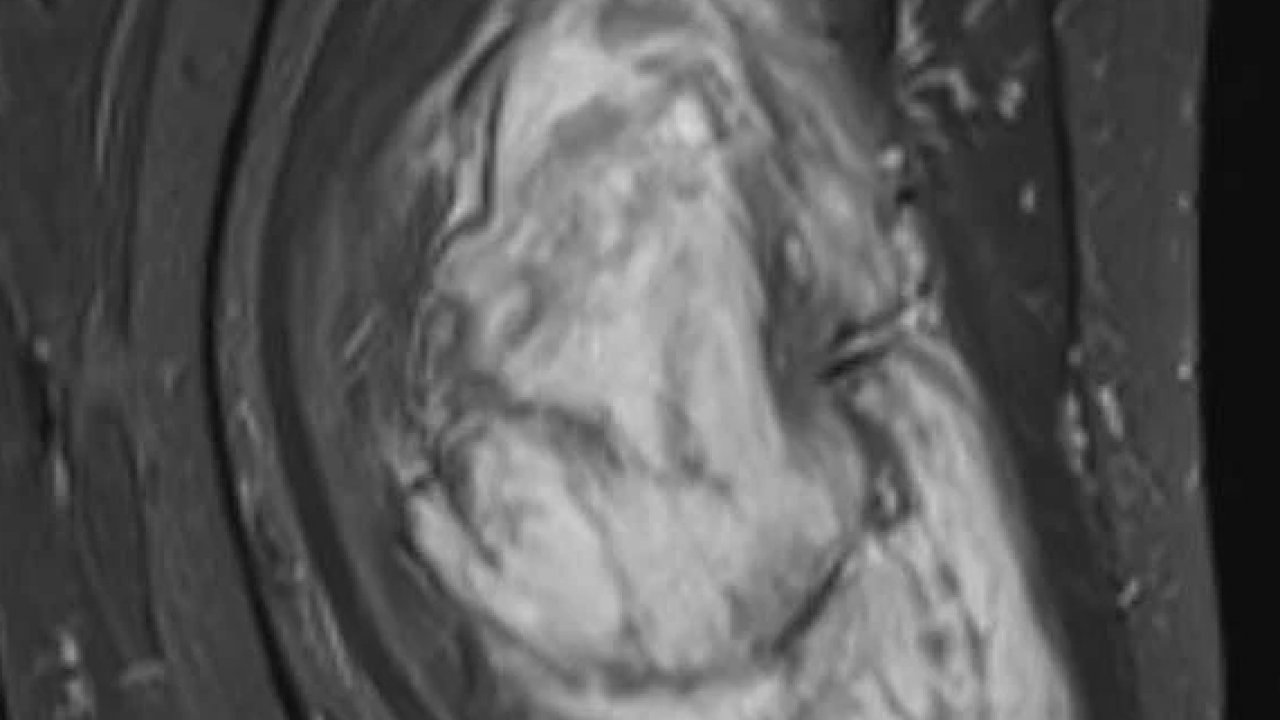

Diyarbakır Dicle Üniversitesi Hastanesi’nde, Mardin’den gelen H.T. isimli kadının bacağından 5 kilo 668 gramlık bir kitle çıkartıldı. Ameliyatı gerçekleştiren Prof. Dr. Emin Özkul meslek hayatındaki çıkarttığı en büyük kitle olduğunu söyledi.

Mardin’de yaşayan H.T. (42), 3 yıl önce sağ baldırının arka kısmında oluşan ve başlangıçta yumurta büyüklüğünde olan kitlenin zamanla büyümesi üzerine Dicle Üniversitesi Tıp Fakültesi Hastanesi Ortopedi ve Travmatoloji Bölümü’ne başvurdu. Muayenede yumuşak doku kitlesi olduğu değerlendirilen şişliğin alınması için Ortopedi ve Travmatoloji Anabilim Dalı Öğretim Üyesi Prof. Dr. Emin Özkul ve ekibi tarafından ameliyat kararı verildi. Yaklaşık 2 saat süren operasyonla kitlenin çıkarıldığı, kitlenin 5 kilo 668 gram geldiği belirtildi.

"Bu hasta da 3 yıl önce fark edilmiş küçük bir kitle, zamanla çok büyük boyutlara, yaklaşık 6 kiloya varan boyutlara varmıştı. Neredeyse bütün bacak boyu yayılan bir kitlesi mevcuttu. Bu kadar büyümenin şöyle sıkıntıları oluyor, kişinin bacağında, kolunda fonksiyon kaybına, yeri geliyor ekstremite kaybına, yani bacağını kaybetmesine yol açabilecek sıkıntılara yol açıyor."

"Küçükken bunlarla baş etmek daha kolay. Kişinin ekstremitesinde, bacağında, kolunda bir sıkıntı yaratmadan bunları telafi etmek, bunları alıp çıkartmak, ameliyatla bunları tedavi etmek daha kolayken bu boyutlara vardığında kişinin bacağında, kolunda fonksiyon kaybı, sakatlık riski çok yüksek oluyor. Bu sebeple küçükken önleminin alınmasında yarar var.” “Hastamızda yaklaşık olarak 3 yıl önce şikayetleri başlamış. Sonra zaman içerisinde hızla büyüyen bir kitleye sahipti. Şanslıydı ki herhangi bir sinirine zarar vermemişti. Hayatına fonksiyon bozukluğu olmadan devam edebilecek. Bölgemize yaşayan ve ülkemizde yaşayan herkese şunu söylüyoruz. Küçük de olsa yumuşak doku kitlelerini önemsemeleri ve uzman görüşü almalarını öneriyorum. Bu hastadan 5 kilo 668 gramlık bir kitle çıkarttık. Bu benim mesleki yaşamım boyunca çıkarttığım en büyük kitlelerden bir tanesiydi. Biraz daha büyük boyutlara varmış olsa kişinin bacağını kurtarma şansınız olmuyor. Bu sebeple bunlara dikkat etmek gerekiyor. Hızlı büyüyen bir kitleniz var ise, ağrısız da olsa mutlaka ve mutlaka tedavi için en yakın sağlık kuruluşuna veya bizim üniversitemizin polikliniklerine başvurabilirsiniz.”